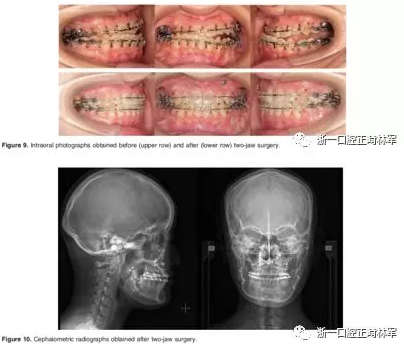

第二阶段:14个月后,进行左侧下颌骨节段性截骨术。在手术中,使用超声骨刀,在左侧后牙区在第一前磨牙处截去3 mm,在第一磨牙区截去6 mm,随后用钛板固定,并立即上0.019*0.025不锈钢丝。下颌合平面和Go-Go'平面从而平行,严重的牙槽骨代偿得以矫正。由于上磨牙和下磨牙之间出现间隙,粘接咬合板以保持颌间间隙,并在这一阶段期间帮助维持左侧咀嚼效能(图7和8)。在这一阶段,患者的面部外观几乎没有变化。

第三阶段:治疗开始26个月后,进行双颌手术。术前持续使用咬合板。行Le Fort I型截骨术和下颌骨矢状劈开术(SSRO),以矫正上颌咬合偏斜、下颌偏斜。

治疗后的头影测量和全景片如图12所示。面部不对称得到改善。牙列中线与面部中线对齐,上下颌拥挤得到解除(图13)。骨性III类关系得到改善(图14)。然而,由于III类关系并未完全矫正,所致的牙齿代偿使得上前牙变得前突。咬合关系改善,双侧尖牙Ⅰ类关系,并建立了理想的覆合和覆盖关系。在双颌手术后一年,固定钛板拆除,左下颌边缘切除2mm的皮质骨突起。随后,她的下颌骨的左右即恢复对称。下颌运动轨迹稳定,尖牙引导合,面部肌肉活动得到很好的平衡(图15)。术后六个月,Semmes–Weinstein评分为1,下牙槽神经瘫痪。